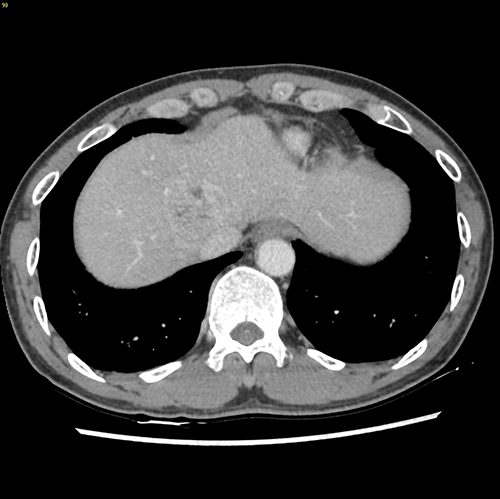

S8肝癌---改良肝中叶切除(3D打印)